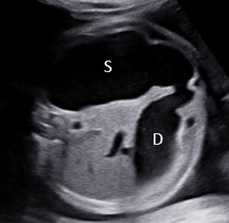

4. Ca thứ tư (Tứ chứng Fallot)

Thai nhi tuần 24 tuần 4 ngày. Hình ảnh siêu âm tim thai như sau:

Hình 8: Tứ chứng Fallot với thông liên thất (TLT) kèm động mạch chủ cưỡi ngựa. Động mạch chủ xuất phát chủ yếu từ thất trái (Điều này khác với thất phải hai đường ra và chuyển vị đại động mạch). Chú ý rằng thành sau động mạch chủ liên tục với lá trước van hai lá (mũi tên màu xanh).

Hình 9: Mặt cắt trục ngắn quanh gốc động mạch chủ. Động mạch phổi xuất phát từ thất phải có kích thước nhỏ so với động mạch chủ (hẹp động mạch phổi). Thấy được thông liên thất (TLT) trên mặt cắt này.